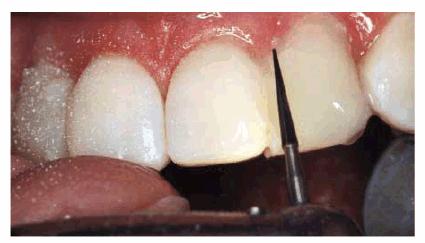

(Figure 24-3C) and mandibular arches (Figure 24-3D). Next, the lateral incisors were

bonded labially to round out a more symmetric arch (Figures 24-3E, and 24-3F

Figure 24-3E: Next, the maxillary laterals were bonded with composite resin and contoured and finished with ET carbide finishing burs (Brasseler).

Figure 24-3F: Better tooth proportion and straighter- appearing teeth can be seen here before the final polishing.